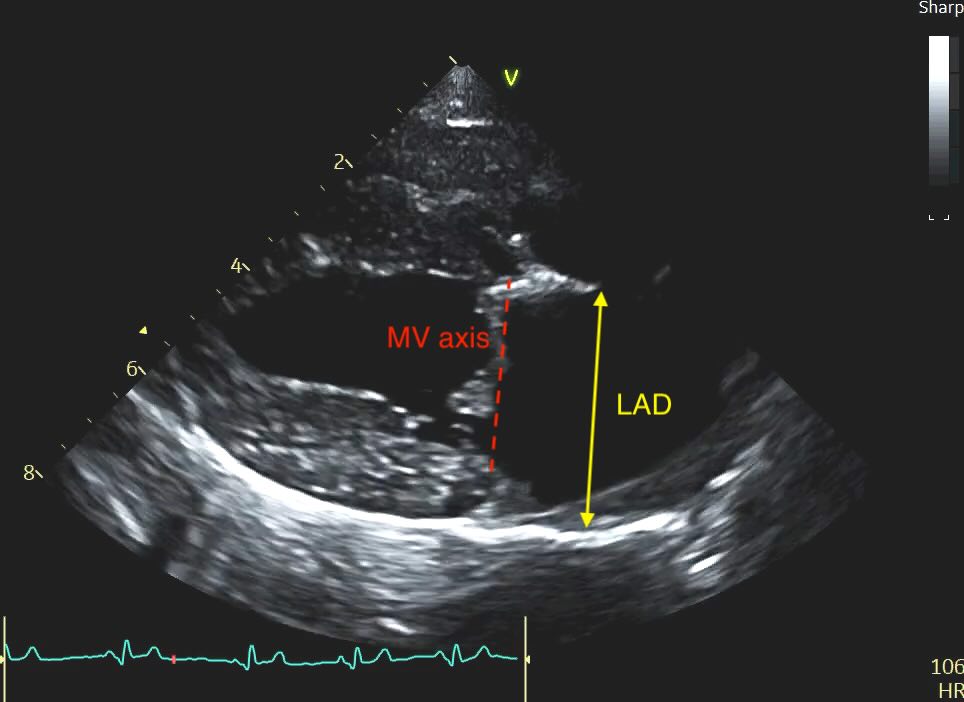

Caliper Placement:

Measure the distance from the inner wall (endocardial border) of the middle of the interatrial septum to the inner wall of the posterior free wall.

The line must be at the widest point of the atrium and must remain parallel to the mitral valve annulus.

The Problem of the “Bowed” Septum

Sometimes you’ll see a distended or “bowed” interatrial septum, often sloping up to the right on the view merging with some dilated pulmonary veins. In a volume-overloaded heart, the high pressure in the left atrium often causes the septum to bulge significantly into the right atrium.

Clinical Recommendation: When the septum is distended, do not measure from the most “sunken” point. Instead, measure from the middle of the septal curvature to the posterior wall, ensuring your line remains strictly parallel to the mitral annulus. Subjectively, a septum that loses its horizontal orientation and “blows out” into the right heart is a strong red flag for elevated filling pressures, even if your linear measurement is borderline.